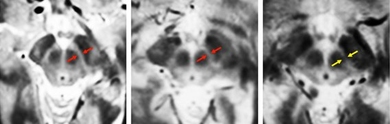

Scientists image brain structures that deteriorate in Parkinson’s

New MRI technique could help doctors track how patients respond to treatment.